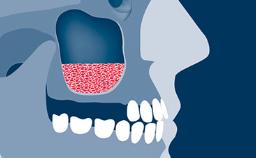

Following tooth loss, alveolar resorption and ongoing pneumatization of the maxillary sinus may lead to vertical bone deficits in the posterior maxilla.

This deficit reduces the distance between the maxillary sinus floor and the alveolar process, so that reconstructing the vertical bone height may be a prerequisite for placement of dental implants of the correct dimensions and in the ideal three-dimensional position while respecting anatomical structures.

Sinus floor elevation is a predictable procedure for vertical bone augmentation in the posterior maxilla that compensates for inadequate bone height. Grafting material is placed into the sinus to increase available bone height and to facilitate the placement of implants of the desired dimensions and in the correct prosthetically driven positions.